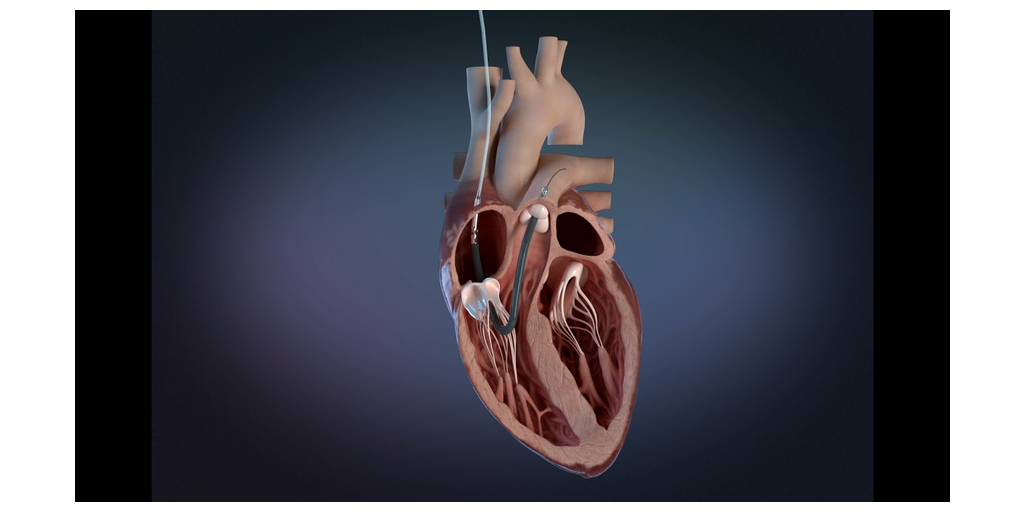

サポーターになって応援しよう!猫の, Impella RP Flex with SmartAssistが右心不全の治療としてFDA,

猫の腎臓病治療薬開発につながる「AIM医学研究」を支援する, Impella RP Flex with SmartAssistが右心不全の治療としてFDA,

Impella RP Flex with SmartAssistが右心不全の治療としてFDA, 腎臓用サプリメント「アゾディル」 | 東久留米 ハル犬猫病院,